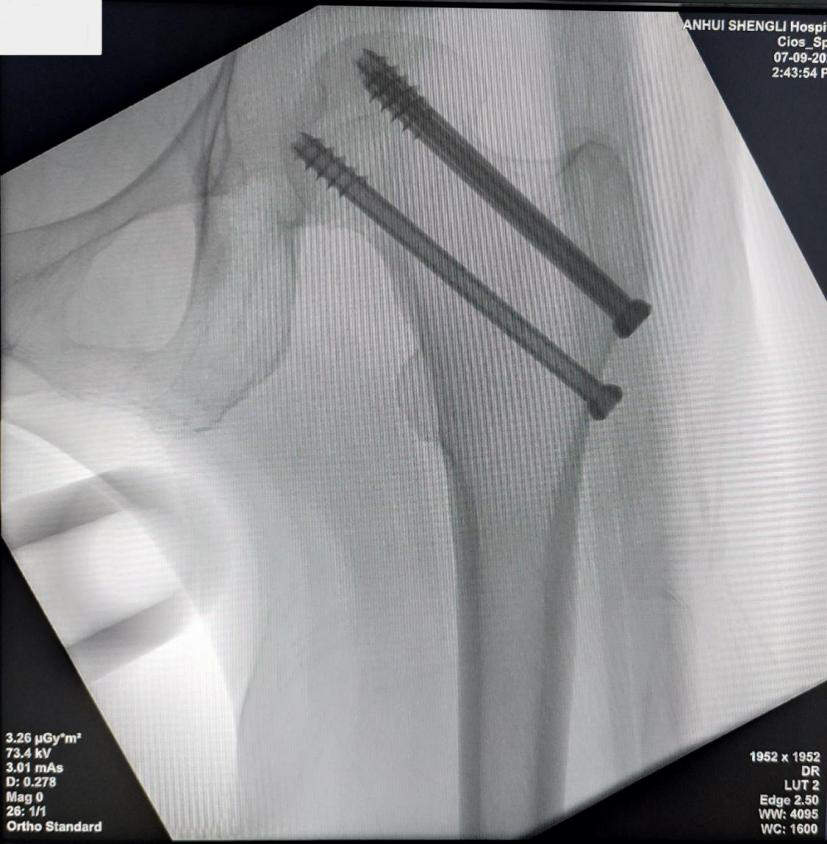

手术当天,在助手配合下,创伤骨科副主任医师徐玮操控骨科机器人,与麻醉科、手术室团队密切协作,利用机器人精准规划入针点及螺钉轨道,稳定、精确置入螺钉,约20分钟手术顺利完成。三天后,高大姐康复出院。

螺钉置入成功透视图